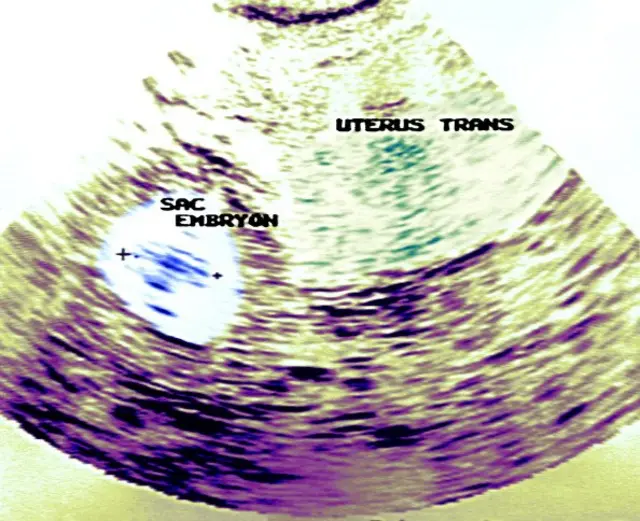

గర్భాశయం పక్కనే ఒక రింగ్ వంటిది కనిపిస్తోంది.

ఎక్టోపిక్ ప్రెగ్నన్సీ.

కొన్ని సార్లు గర్భాశయంలో కాకుండా, పక్కనే వున్న ట్యూబులో వస్తుంది ప్రెగ్నన్సీ.

ట్యూబు పరిమాణం సన్నగా వుంటుంది గనక, అందులో పిండం రెండు నెలల మించి పెరగలేదు.

వర్షిత స్కాన్లో అదెంత సైజో చూస్తోంది. "మేడం, 4.2 సెంటీమీటర్ " అంది.

అతి చిన్న పిండం. దానిలో మినుకు మినుకుమంటూ హార్ట్ బీట్.

ట్యూబులో వచ్చిన ప్రెగ్నన్సీ చిన్నదైతే కొన్ని సార్లు ఇంజెక్షన్ ద్వారా చికిత్స చేయొచ్చు.

పరిమాణంలో 3.5 సెమీ మించి ఉన్నా, దానిలోపల హార్ట్ బీట్ కనిపించినా వీలైనంత త్వరగా దాన్ని ఆపరేషన్ ద్వారా తొలిగించాల్సి ఉంటుంది. వెంటనే చికిత్స చేయకపోతే, కొన్ని సందర్భాలలో, ట్యూబు పలిగిపోయి ప్రమాదమవుతుంది.

"అవును. అలా కూడా ట్రీట్మెంట్ ఇవ్వొచ్చు. కానీ గర్భం సైజు 35 మిమీ కన్నా తక్కువ వుండాలి. ప్రెగ్నన్సీ హార్మోన్ లెవెల్ 1500 నుండి 5000 మధ్యలో వుండాలి. అన్నిటికన్నా మించి ఆ పిండంలో హార్ట్ బీట్ కనిపిస్తే ఇంజెక్షన్ ద్వారా చికిత్సకు ప్రయత్నించకూడదు. ఆపరేషనే సరైన ట్రీట్మెంట్."